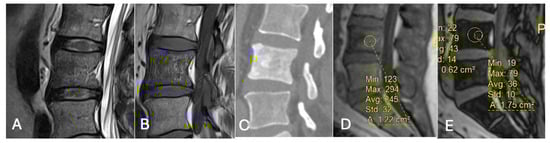

- Differentiating Red Marrow Reconversion from Metastasis: Red marrow reconversion may mimic metastatic infiltration on T1-weighted images but retains microscopic fat and hence shows significant signal drop on CSI, unlike true metastases [40] (Figure 21).

Figure 21. Focal marrow hyperplasia in L4. Sagittal T1 (A), T2 (B), CT (C), and chemical shift (D,E), showing heterogeneous signal on T1 and T2 and sclerosis on CT with significant signal drop on chemical shift images (D,E). - Characterising Indeterminate Marrow Lesions: In patients with cancer, incidental marrow lesions often cause clinical concern. CSI helps identify those lesions with retained fat, reducing the need for biopsy or further imaging such as bone scan or positron emission tomography (PET) [39] (Figure 18).